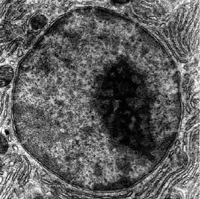

নিউক্লিয়াস (ইংরেজি: Cell Nucleus) বা কেন্দ্রিকা হল প্রোটোপ্লাজমের সবচেয়ে ঘন, পর্দাঘেরা এবং প্রায় গোলাকার অংশ।যা কোষের সব জৈবনিক ক্রিয়া বিক্রিয়া নিয়ন্ত্রণ করে তাকে বলা হয় নিউক্লিয়াস ৷ রবার্ট ব্রাউন(Robert Brown) সর্বপ্রথম ১৮৩১ সালে কোষে নিউক্লিয়াস দেখতে পান এবং এর নামকরণ করেন।তিনিই এটি আবিষ্কার করেন সর্বপ্রথম। এটি ৪ টি অংশে বিভক্ত।

কোষ জীববিজ্ঞানে, নিউক্লিয়াস (নিউক্লিয়াস; ল্যাটিন নিউক্লিয়াস বা নিউকিউলিয়াস থেকে যার অর্থ বীজ) হল ইউক্যারিওটিক অর্থাৎ প্রকৃতকোষে পাওয়া একটি ঝিল্লি-আবদ্ধ অঙ্গাণু। প্রকৃতকোষে সাধারণত একটি একক নিউক্লিয়াস থাকে। তবে কোষের ধরন অনুসারে,যেমন স্তন্যপায়ীর লাল রক্তকণিকা(লোহিত রক্তকণিকা)-র কোনো নিউক্লিয়াস থাকে না আবার অস্টিওক্লাস্ট সহ আরও কয়েক ধরনের কোষ বহুনিউক্লিয়াসবিশিষ্ট হয়ে থাকে।

নিউক্লিয়াস তৈরির প্রধান কাঠামো হলো এর বহিঃপর্দা, এটি মুলত একটি দ্বিস্তরী মেমব্রেন বা পর্দা যা সমগ্র নিউক্লিয়াসটিকে ঘিরে রাখে এবং কোষীয় সাইটোপ্লাজম থেকে এর বিষয়বস্তুকে বিচ্ছিন্ন করে। এবং নিউক্লিয়ার ম্যাট্রিক্স অর্থাৎ মাতৃকা (যার মধ্যে নিউক্লিয়ার উপাদানসমূহ রয়েছে) ও সাইটোপ্লাজমের মধ্যে একটি নেটওয়ার্ক হিসেবে কাজ করে। যা নিউক্লিয়াসকে যান্ত্রিক সমর্থনদেয়। নিউক্লিয়াসই সম্পূর্ণ কোষের কার্যাবলী নিয়ন্ত্রণ করে,তাই একে বলা হয় কোষের মস্তিষ্ক। নিউক্লিয়াসের অন্যতম কাজ বংশগতীয় বস্তু বহন করা।